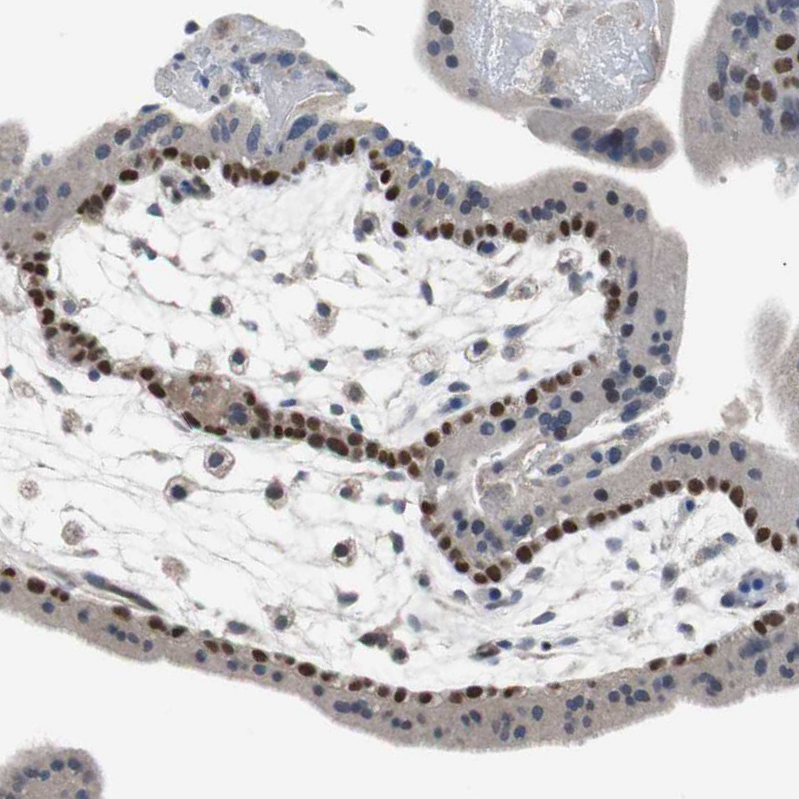

Immunohistochemistry analysis in human skin and kidney tissues using HPA006288 antibody. Corresponding TP63 RNA-seq data are presented for the same tissues.